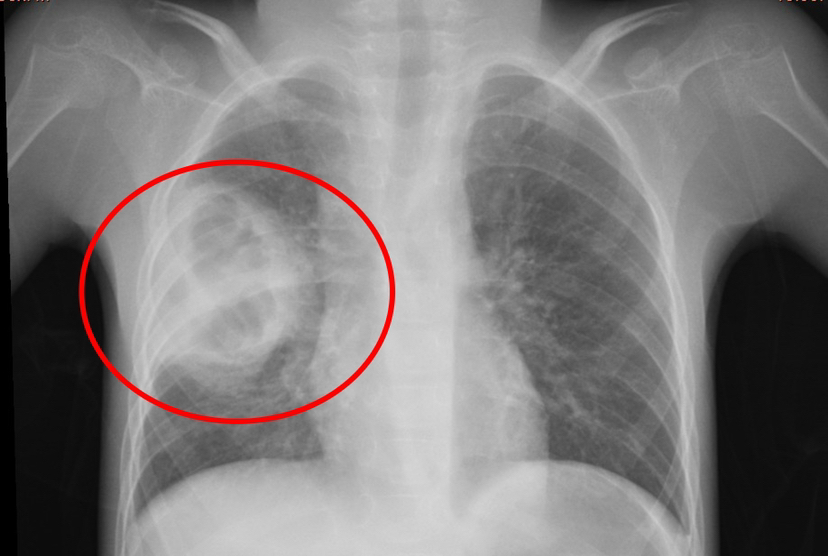

患儿小小,患有脑瘫与药物难治性癫痫,重度营养不良,7岁体重仅10公斤,因长期卧床导致肺部感染并发肺脓肿,入院时情况极为复杂,胸部CT显示肺脓肿、肺炎合并胸腔积液,高热不退、呼吸困难,惊厥频发,治疗难度极大,家属几近绝望,甚至动过放弃治疗的念头。